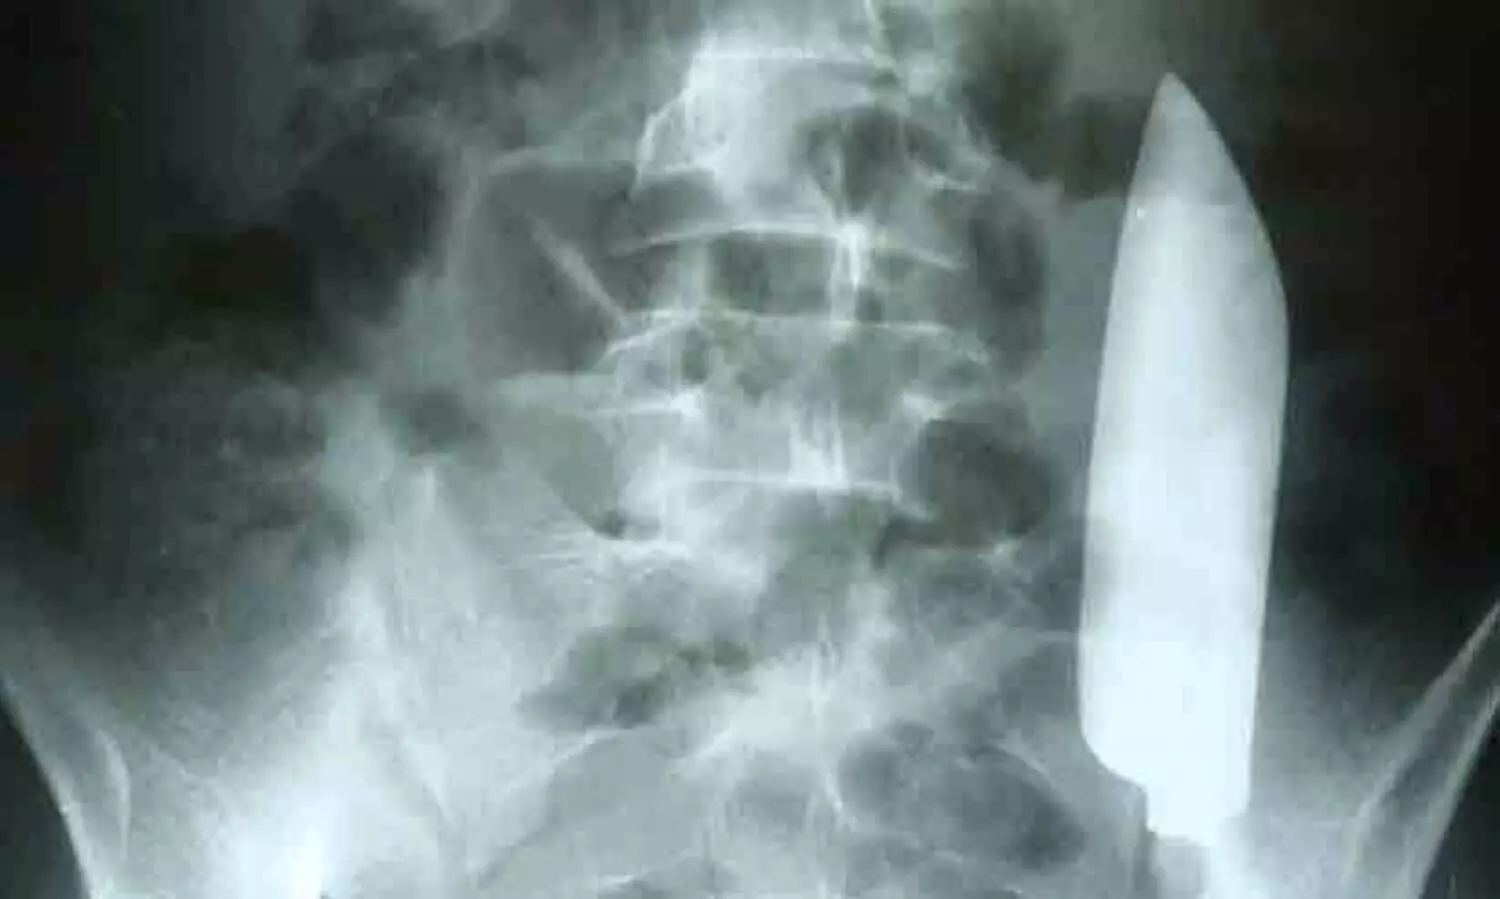

വയറുവേദനയുമായെത്തിയ യുവാവിന്റെ വയറ്റിൽ നിന്ന് പുറത്തെടുത്തത് കത്തി